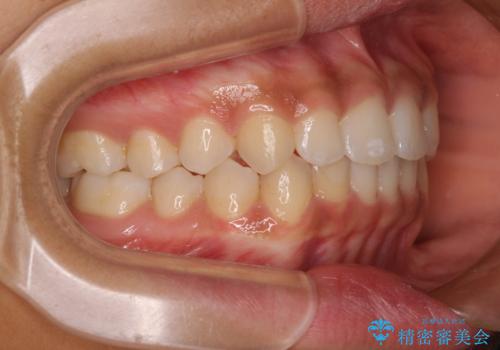

前歯のデコボコを治したい インビザライン・モデレートによる矯正治療

- 上下前歯の叢生を気にして来院された患者様です。

インビザラインでの治療を希望されていて、デコボコの程度が中等度であり、安価なパッケージにて対応可能と判断されたため、インビザライン・モデレートを用いて矯正治療を行うこととしました。